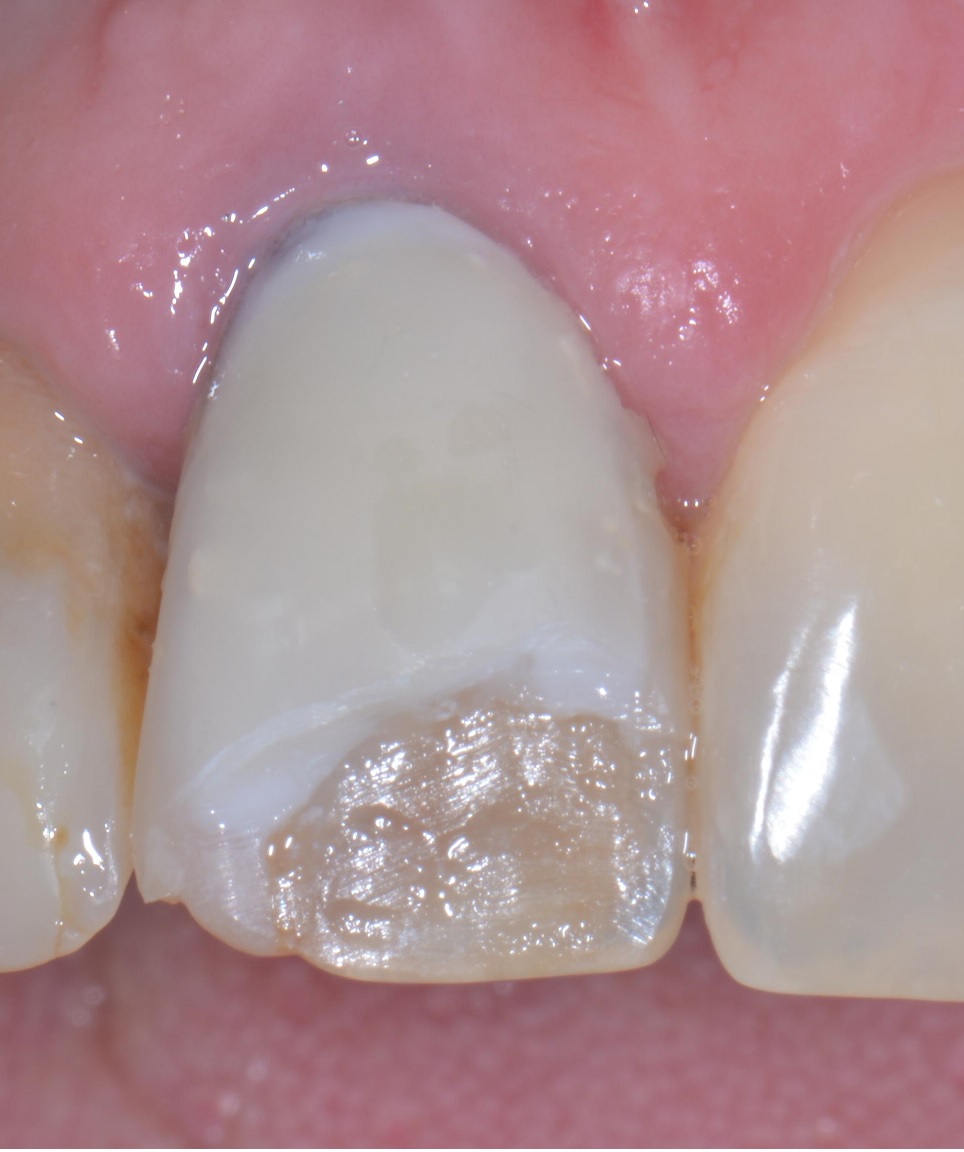

Il dente della signora aveva un perno dentatus a vista dal lato palatino, era discromico, è stato lasciato il vecchio composito sotto la nuova pregiata faccetta, ha il colore sbagliato e andava fissato un appuntamento di revisione per decenza prima di chiedere 250 euro. E poi il 21 ha una carie, il 12 è devitalizzato e deve contenere all’interno una di quelle schifezze di paste di medicazione nere. Il 15 e il 16 anche solo facendo aprire la bocca alla paziente si vede che hanno qualcosa che non va e la paziente mi ha detto “ah, sì, quello mi ha fatto malissimo e il dentista ha detto che la prossima volta vediamo un po’ se si riesce a recuperare, ho già un appuntamento ma a questo punto non vado più e vengo da voi…”